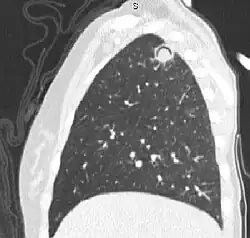

CT w projekcji strzałkowej klatki piersiowej 14-letniej dziewczynki z ostrą białaczką mieloblastyczną. W górnym prawym płacie płuca widać zmianę, odpowiadającą obrazowi grzybniaka w przebiegu infekcji Aspergillus

Objaw powietrznego rąbka w kształcie półksiężyca – objaw radiologiczny występujący na zdjęciach rentgenowskich i obrazach w tomografii komputerowej klatki piersiowej jako półksiężycowaty obszar, przepuszczalny dla promieniowania rentgenowskiego spowodowany przez obecność okrągłej masy nieprzepuszczalnej dla promieniowania w jamie płuca wypełnionej powietrzem[1]. Klasycznie spowodowany przez grzybniaka kropidlakowego (jedna z postaci aspergilozy) w płucu. Dochodzi do tego gdy Aspergillus skolonizuje jamę płuca (np. pogruźliczą)[2].